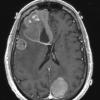

NEOPLASMS (METASTASES)